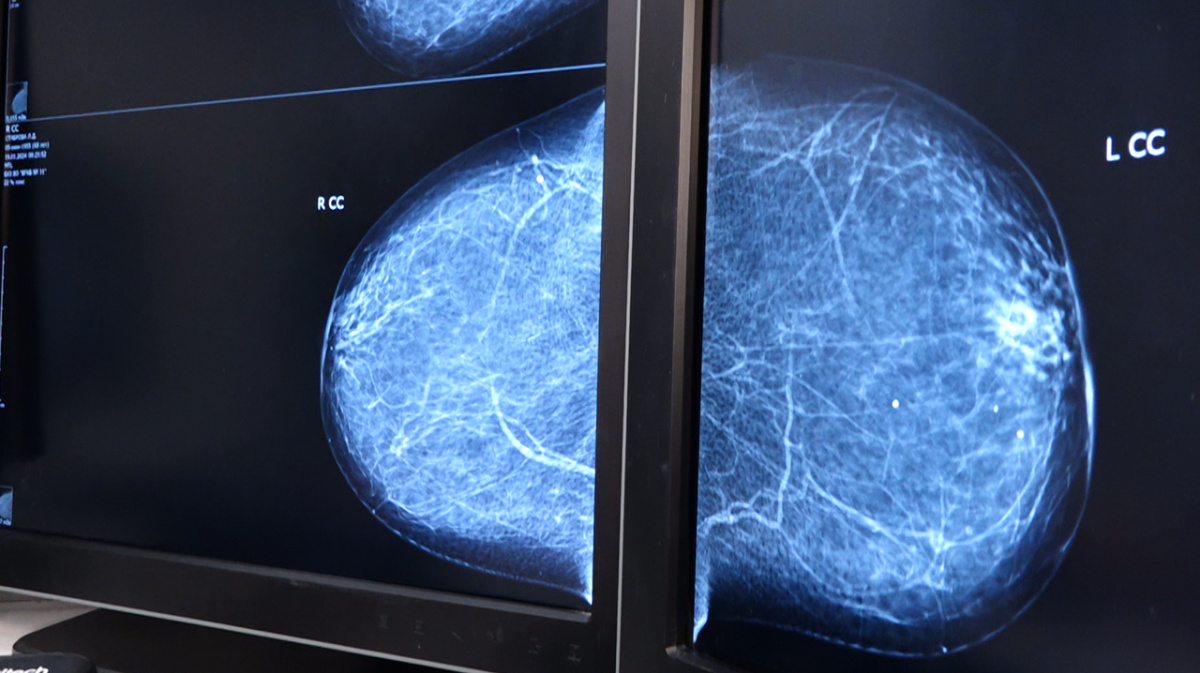

Искусственный интеллект поможет сократить очереди в воронежских поликлиниках, а врачам – ставить диагнозы точнее. Но пока только в отделениях лучевой диагностики. Там технологию уже используют для анализа маммографических исследований – их проводят для выявления рака молочной железы.

Когда изображение попадает в единую базу, к его анализу подключается искусственный интеллект. Через 15 минут все необходимые сведения уже у врача: предварительное заключение, плотность железы, состояние кожи, лимфоузлов, наличие различных новообразований. Их алгоритм отмечает специальными маркерами.

В планах на 2024 год — расширить возможности программы и использовать её для анализа флюорографических снимков и изображений компьютерной томографии. Алгоритм снижает риск проглядеть какую-либо патологию — выявляет изменения с точностью до 95% процентов. Но это лишь подспорье для врачей — окончательный диагноз они по-прежнему должны ставить самостоятельно.

Скоро искусственный интеллект начнут использовать для анализа КТ-исследований и флюорографии. В течение 10 минут робот составляет протокол с описанием полученного результата и предполагаемым диагнозом. Применение модуля ИИ на 15% улучшает качество диагностики по сравнению с чтением снимка.  Виталий Власов